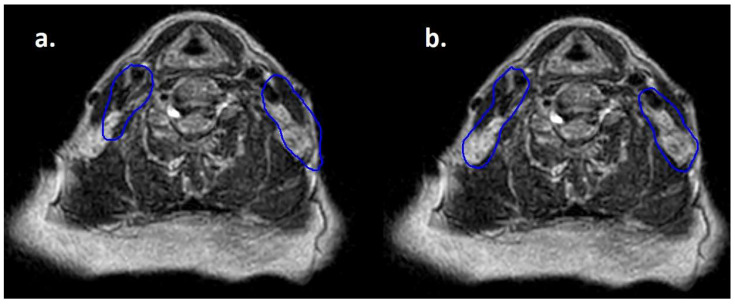

Purpose: Lymphomas are generally radiosensitive; therefore, disease volume tends to shrink during radiotherapy courses. As MRI-linac provides excellent soft tissue definition and allows daily re-contouring of gross tumor volume and clinical target volume, its adoption could be beneficial for the treatment of lymphomas. Nonetheless, at this time there is a lack of literature regarding the use of MR-linac in this context. Methods: A prospective observational study was conducted on patients affected by non-Hodgkin lymphoma (NHL) involving head and neck (H&N) sites and treated with Elekta Unity® MR-Linac. The clinical and dosimetric data of the first eight patients were collected and integrated with relevant data from medical records. Results: Seven patients had B-cell lymphoma (three DLBCL, two MALT, one follicular, and one mantle-cell) and one T-cell/NK lymphoma. The intent of RT was radical for four patients, salvage treatment for three, and CAR-T bridging for one. Two patients presented orbital localizations and six cervical lymphonodal sites. Median GTV was 5.74 cc, median CTV 127.01 cc, and median PTV 210.37 cc. The prescribed dose was 24-50 Gy in 2 Gy fractions for seven patients and 24 Gy in 3 Gy fractions for one patient. All the patients experienced acute toxicity, the maximum grade was G1 for five patients and G2 for three at the end of RT. One month after radiotherapy seven patients still experienced G1 toxicity, but no toxicity grade ≥ 2 was reported. First radiological assessment was performed for all the patients after a median of 101.5 days, reporting complete response in all the cases. After a median follow up of 330 days, no patient experienced local disease progression, while one patient developed distant progression. Conclusions: radiotherapy for NHL with H&N localization using a 1.5 T MR-linac was feasible, with no >G2 toxicity and optimal response rate and disease control.